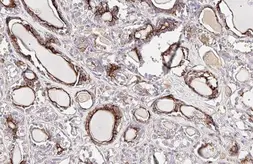

Description Rabbit MonoclonalApplications WB ICC/IF IHC-PReactivity Hu, Ms, RatSummary This antibody was raised against human Carbonic Anhydrase IX Extracellular domain.